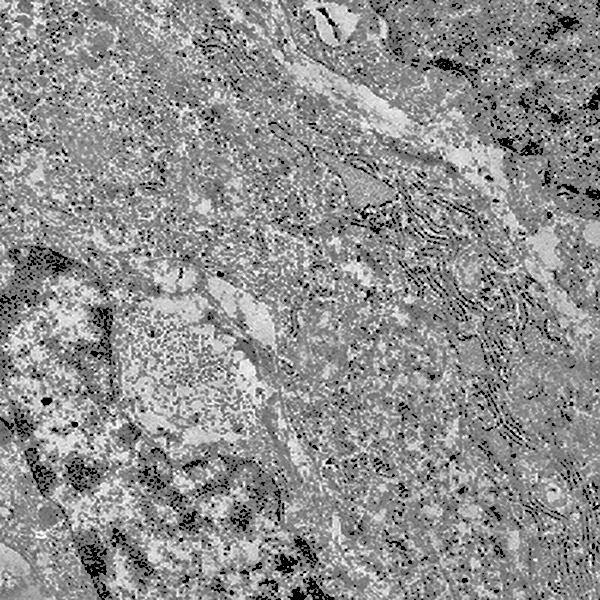

Al microscopio elettronico l’ergastoplasma in stato di stress appare con cisterne dilatate e ricolme di materiale amorfo, debolmente elettropaco.

Anche nelle cellule dei gliosarcomi quì rivisitati, si repertano disfunzioni ergastoplasmatiche; infatti si evidenziano tratti della rete ergastoplasmatiche con cisterne dilatate e ricolme di materiale amorfo, debolmente elettropaco. In un minor numero di cellule questa disfunzione si appalesa sotto forma di fasci iperdensi di sub strutture ergastoplasmatiche variamente orientate,spesso con cisterne ectasiche e occupanti una ampia area del citoplasma.

Fig.8  Fig.9